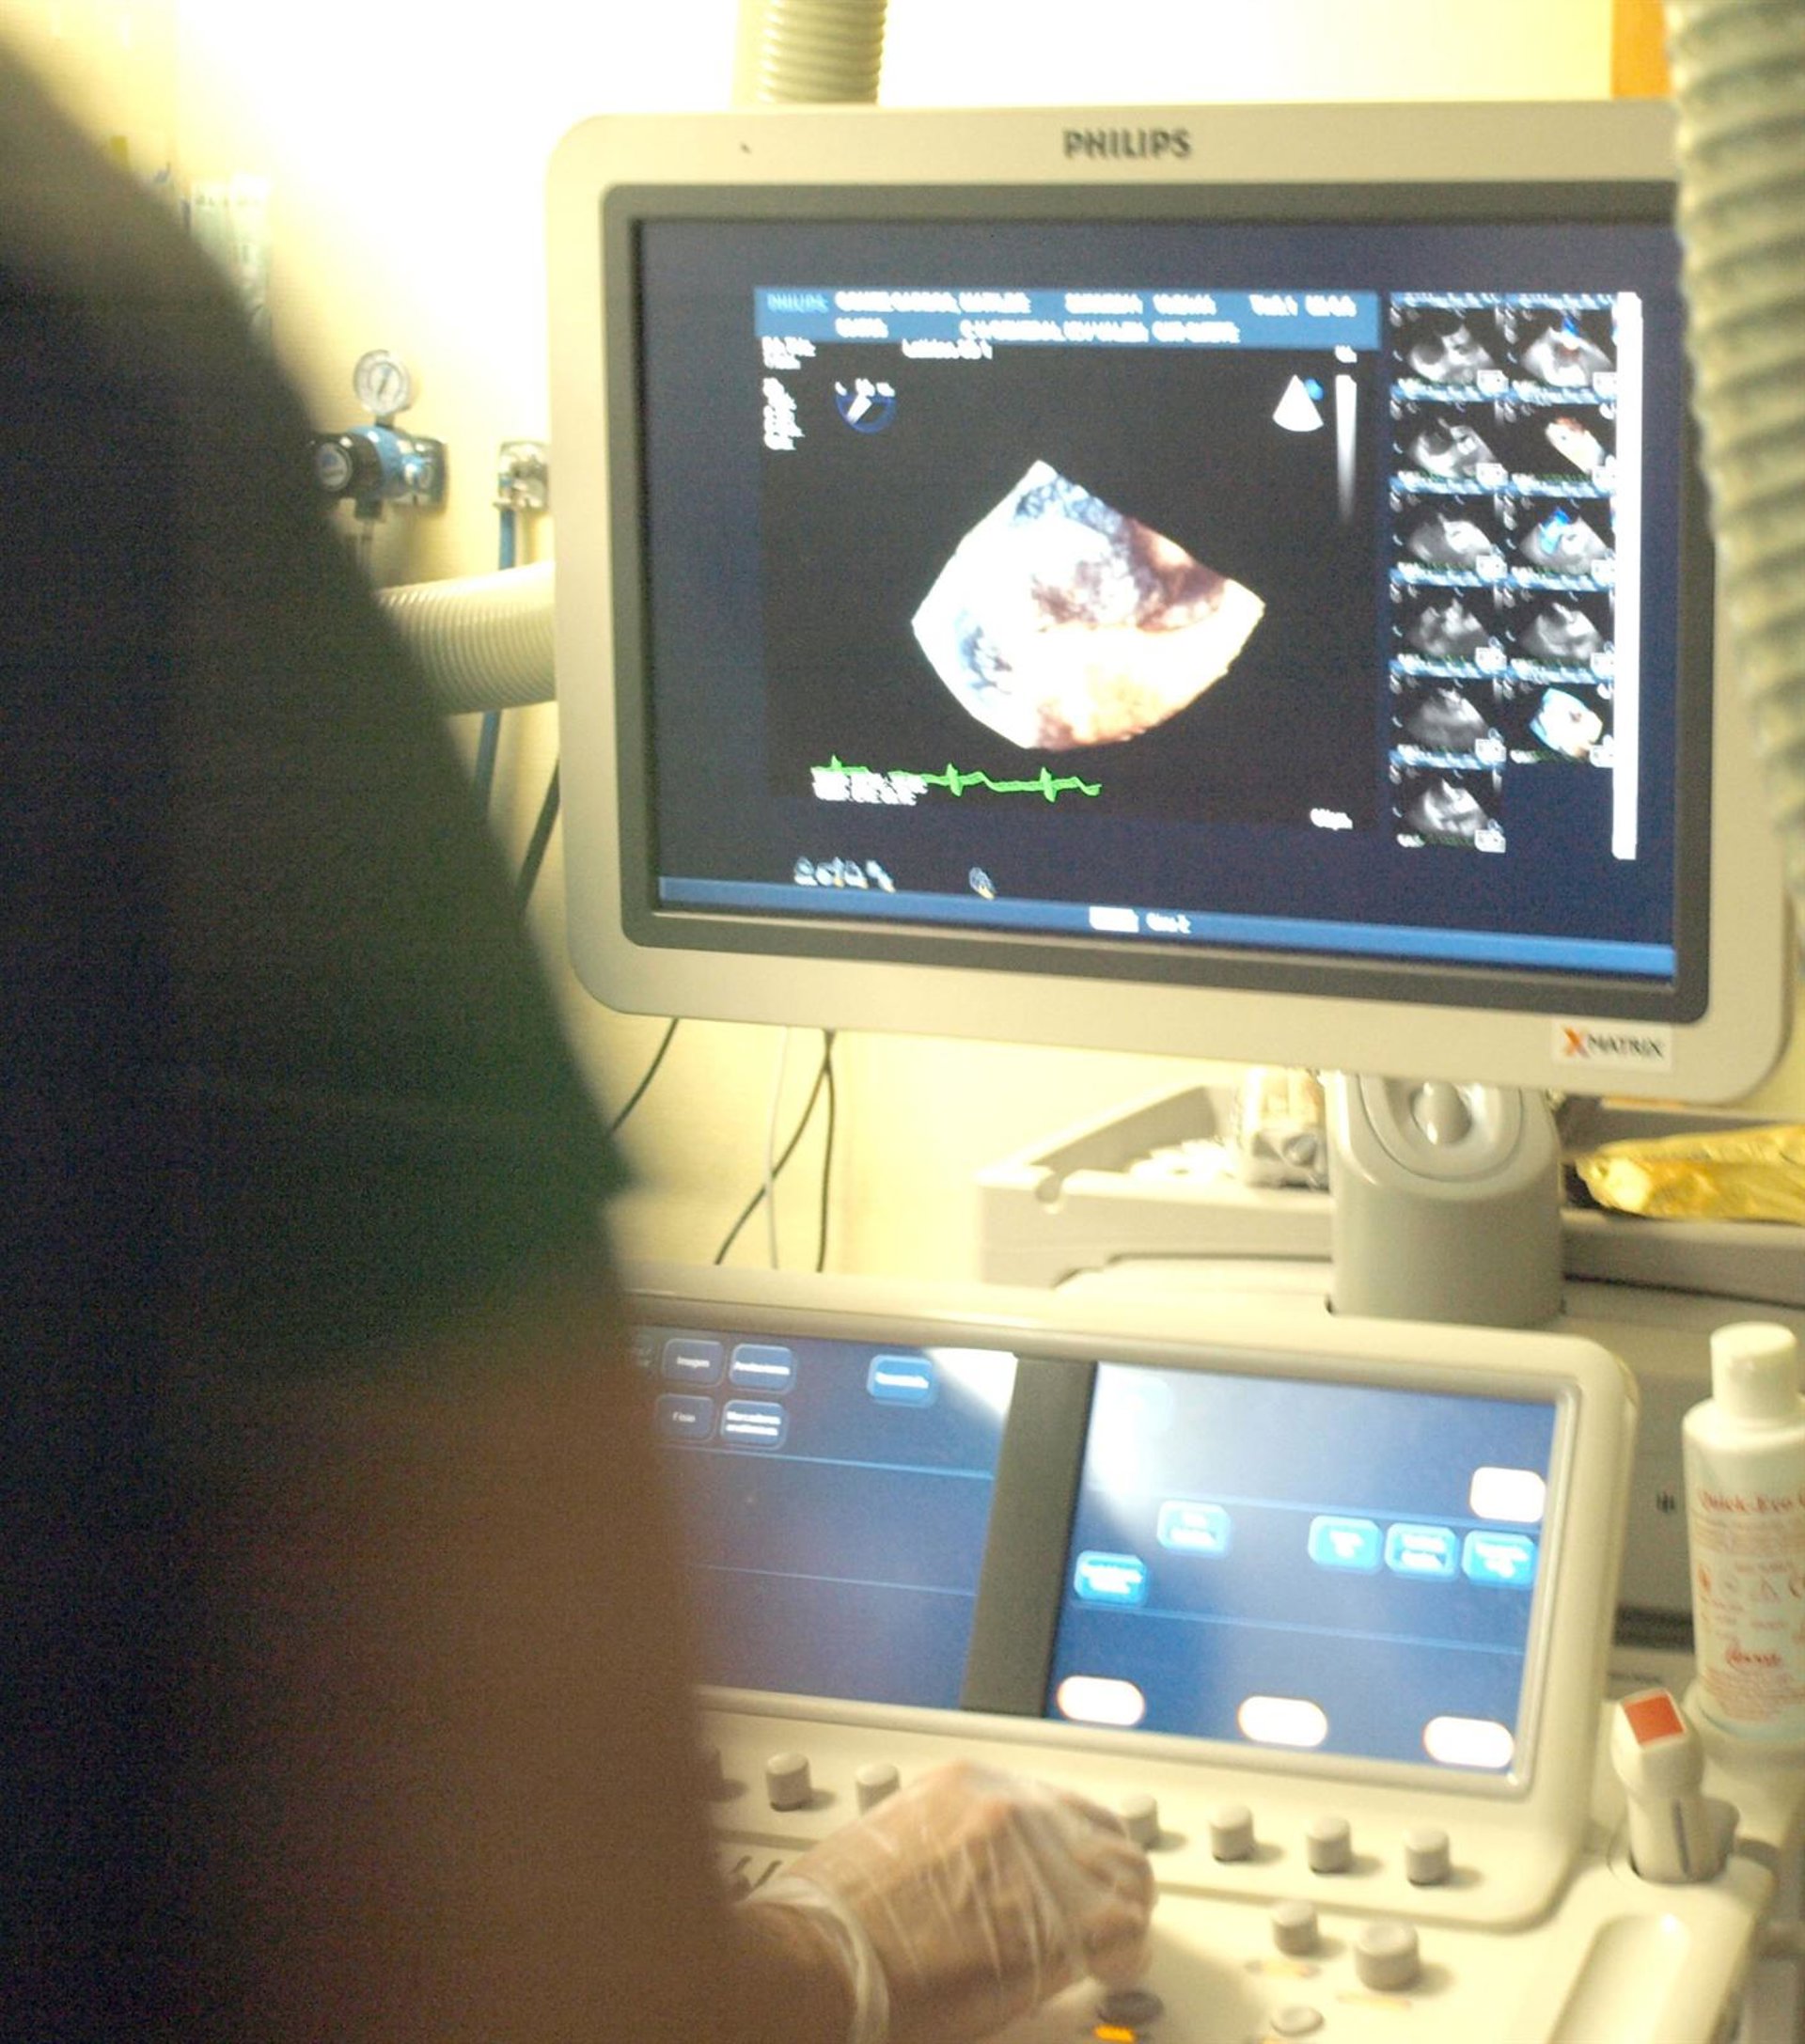

El Instituto Cardiovascular del Hospital General de Valencia ha incorporado los últimos avances tecnológicos en el diagnóstico por la imagen. Concretamente, en Cardiología se ha incorporado la ecocardiografía tridimensional en tiempo real, es decir, en cuatro dimensiones, según ha informado el centro hospitalario en un comunicado.

La eococardiografía tridimensional en tiempo real adquiere, de forma instantánea, la imagen en tres dimensiones. "De este modo, permite el mapeo rápido del órgano porque es posible visualizar, al mismo tiempo, múltiples planos superpuestos que se pueden consultar de forma interactiva", ha explicado el director del Instituto Cardiovascular, Juan Martínez-León.

Con la visualización simultánea de imágenes múltiples al mismo tiempo se puede examinar la forma anatómica cualquier estructura. Además, posibilita un análisis de los volúmenes cardiacos, de la masa ventricular e, incluso, de miocardio con anormalidades de contracción o perfusión.

La ecocardiografía tridimensional en tiempo real abre posibilidades de la cardiología no invasiva y también es útil para investigación clínica de las enfermedades cardíacas.